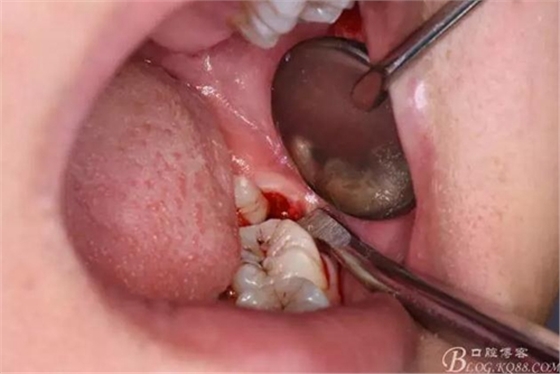

圖7.高速渦輪鉆分牙

圖8.先從頸部橫斷38

圖9.再把38牙冠近遠中縱斷